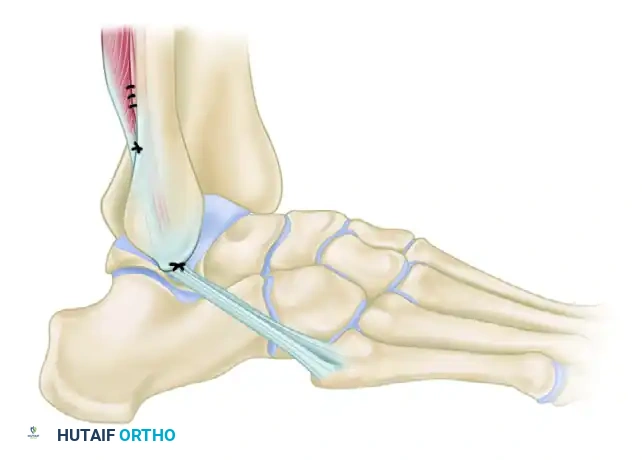

4. Tendon Routing and Fixation

The routing of the tendon is the defining characteristic of the Watson-Jones procedure, creating a mechanical block to anterior talar translation.

- First Pass (Fibula): Guide the mobilized peroneus brevis tendon through the first tunnel in the lateral malleolus, passing it from posterior to anterior.

- Second Pass (Talus): Pass the tendon through the second tunnel in the talar neck, routing it from inferior to superior.

- Tendon Flattening: Unroll the remainder of the tendon to make it flat. This increases the surface area for healing and reduces the bulk of the final construct.

- Final Routing: Carry the flattened tendon posteroinferiorly across the lateral surface of the lateral malleolus.

- Periosteal Preparation: Make an oblique incision through the periosteum on the lateral aspect of the malleolus at the level where the tendon crosses.

FIGURE 89-26 A: Modified Watson-Jones technique demonstrating the routing of the peroneus brevis tendon through the fibula and talus, effectively reconstructing the anterior talofibular ligament vector.

- Tensioning and Fixation:

- Hold the ankle in neutral dorsiflexion (0 degrees) and slight eversion (approx. 5 degrees). Do not overtension in excessive eversion, as this will lock the subtalar joint.

- Suture the tendon to itself (creating a closed loop) and to the robust periosteum on the posterior aspect of the malleolus using heavy non-absorbable sutures (e.g., #0 or #2 FiberWire or Ethibond).

- Suture the incised periosteum over the tendon on the lateral side of the malleolus to further secure the construct and promote biological integration.